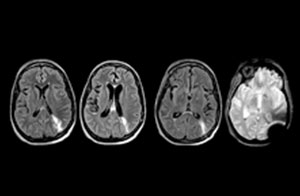

“Avant, nous réalisions des examens TDM en raison de leur disponibilité et de leur rapidité”, admet le Dr Karis, “mais si une IRM pouvait être aussi efficace qu’une TDM, les médecins traitants préféreraient probablement, dans certains cas, l’IRM à la TDM. Réduire le nombre d’examens TDM chez les patients de moins de 40 ans ne présentant aucun signe de trouble grave, comme un AVC, était également une des principales raisons justifiant l’introduction de l’IRM dans le service d’urgences. “L’IRM est un examen plus efficace pour identifier les lésions des tissus mous dans le cerveau. Ce qui a vraiment influencé la décision d’un point de vue administratif, c’est la dose de rayonnement totale à laquelle sont exposés les patients du service d’urgences, et la possibilité de la réduire en y introduisant l’IRM.”

Pour minimiser la durée des acquisitions, des protocoles d’examen IRM rapides (ExamCards) ont été mis au point. Ils réduisent la durée d’acquisition totale à moins de 10 minutes pour certains examens. Des techniques comme le mDIXON (DIXON modifié) sont utilisées pour une acquisition solide des images d’IRM sans graisse dans l’environnement stressant des urgences.

“Nous utilisons beaucoup le mDIXON TSE dans notre imagerie du rachis en service d’urgences”, déclare le Dr Karis. “Ce qui est particulièrement appréciable, c’est sa fiabilité par rapport au type de susceptibilité des problèmes pouvant survenir avec des images spectrales classiques saturées en graisse ; ces problèmes sont essentiellement éliminés grâce à la technique mDIXON. C’est vraiment un avantage de disposer de l’imagerie sans graisse nécessaire à la technique mDIXON dans notre service d’urgences.”